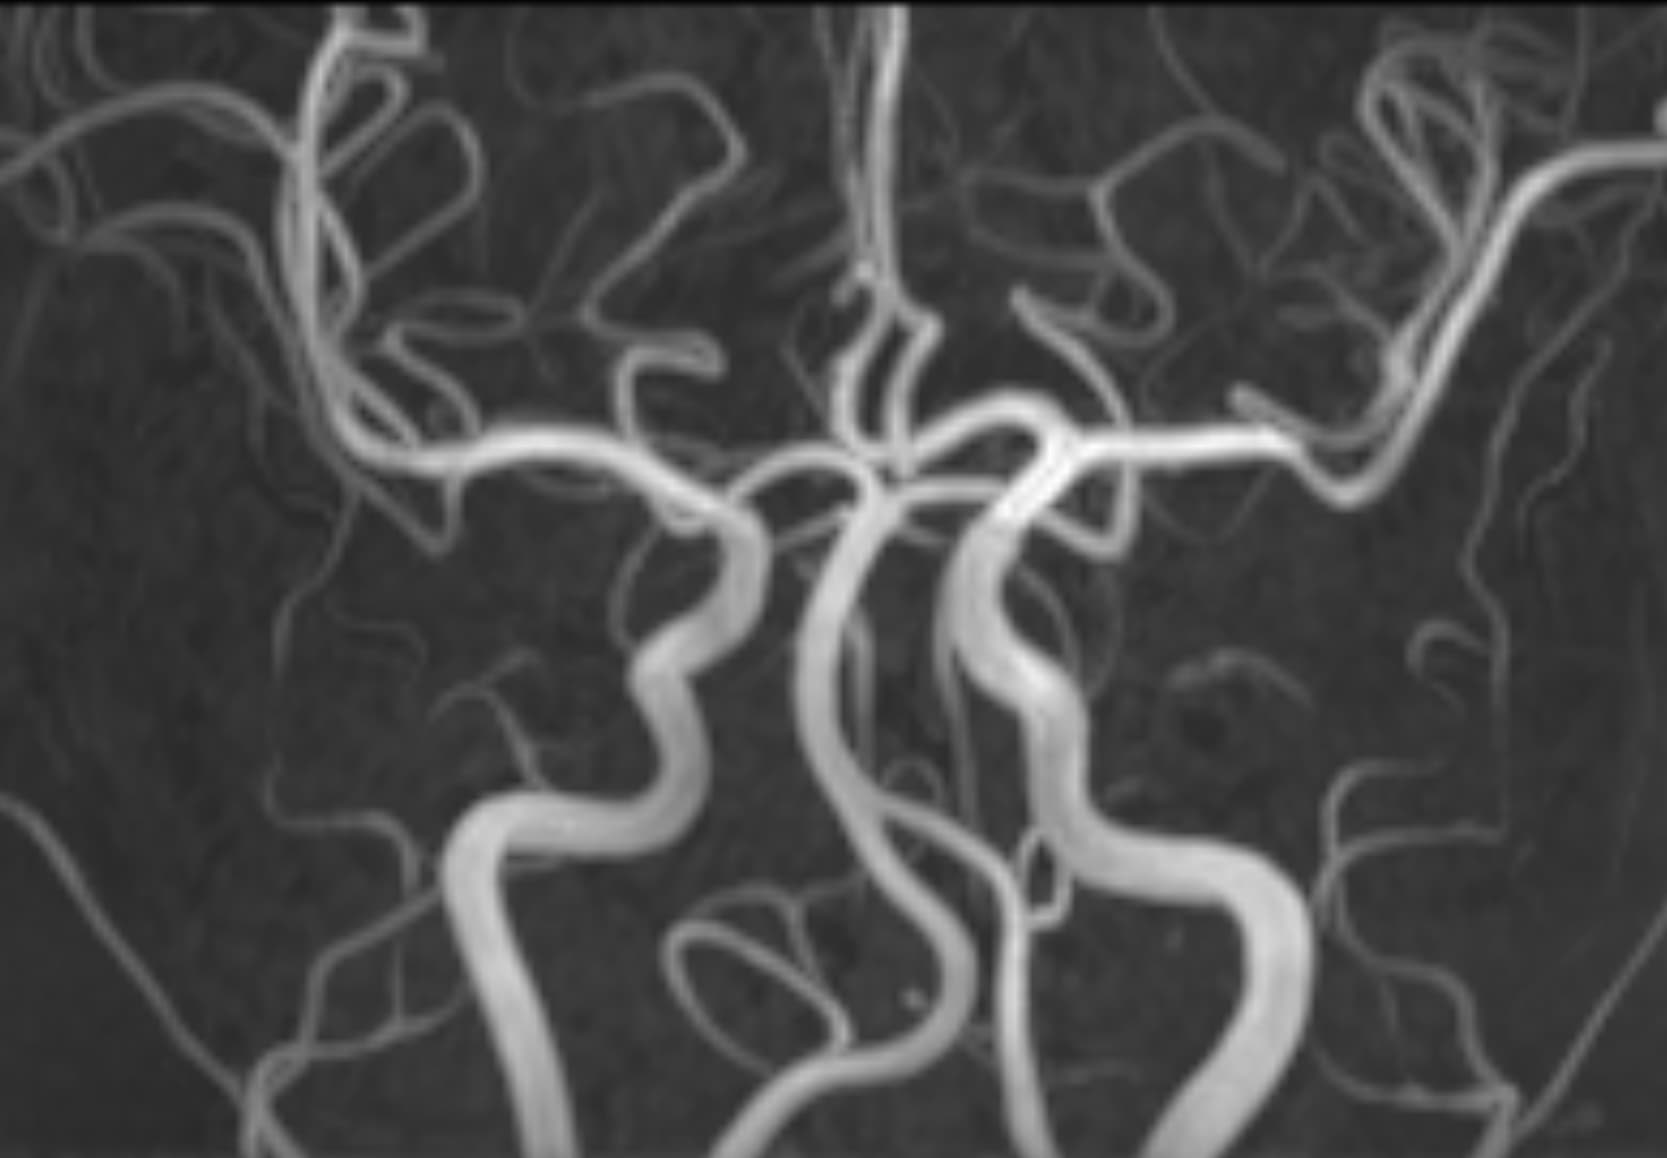

See real-world examples of SwiftMR™ across various MRI systems and anatomical regions

Scan time 03:14

Scan time 02:07

Scan time 03:08

Scan time 1:12

Scan time 04:53

Scan time 1:46